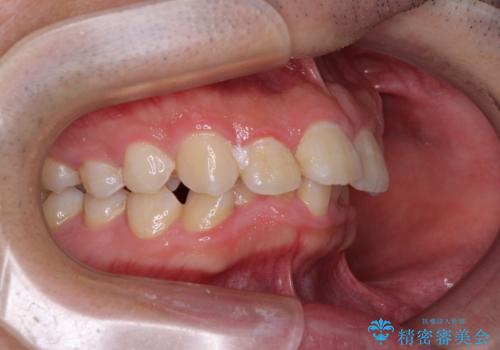

- デコボコと奥歯の咬み合わせのズレを気にして来院された患者様です。

骨格的に、下顎が右側にずれており、左側の咬み合わせに鋏状咬合などのアンバランスが生じている状態でした。

また、上顎前歯に欠損が1本あり、上下ともに前歯部に叢生が認められ、下顎前歯の大半が隠れてしまうほどの過蓋咬合も認められました。

咬合平面を平坦にしながら前歯の咬み合わせを挙上し、デコボコと鋏状咬合も改善していくこととしました。